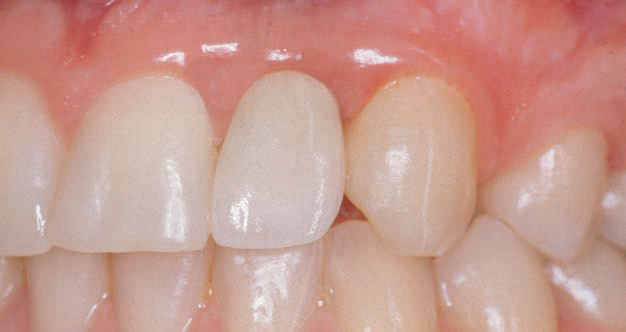

Porcelænskronen er sat fast på implantatet. Tandrækken er nu intakt.